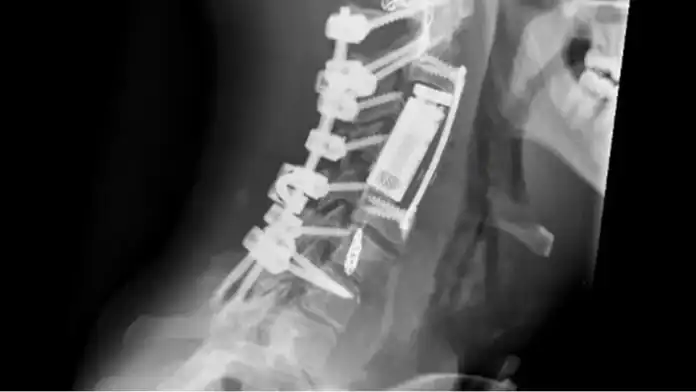

تثبيت خلفي للفقرات من C1 حتى C7

تحرير النخاع الشوكي وتأمين استقرار العمود الفقري

استئصال كامل للورم والفقرات المصابة بطريقة “الاستئصال الكامل بكتلة واحدة” من الجهة الأمامية

تعويض الفقرات باستخدام قفص فقري تمددي وتثبيت أمامي للثبات التام